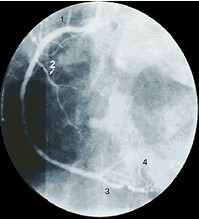

右前斜头位: 左冠状动脉

1、第一边缘支 2、回旋支 3、对角支 4、前降支 可帮助看清左前降支的远端2/3。 |